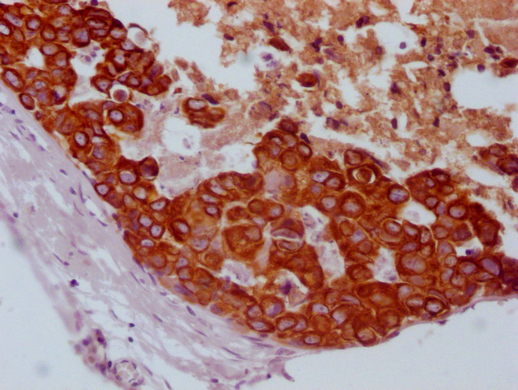

Human tonsil tissue

1:100